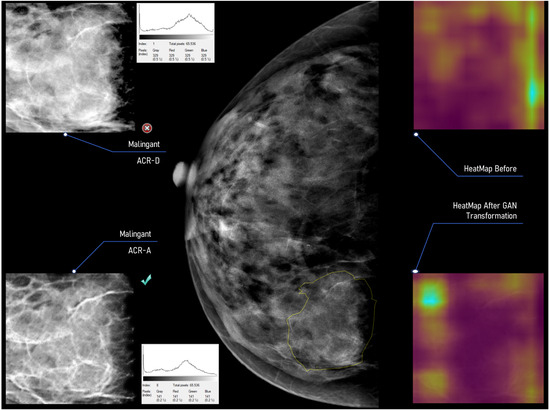

A depiction of the system response utilizing a full mammographic image can be seen in Figure 18 and Figure 19. Figure 18 showcases six notable areas before and after the ACR category transformation to the ACR-A class. According to the database annotations, the findings are enclosed in the gray outline region. At first, the CNN classifier accurately identified four marked regions (Violet tick mark) as Benign/Malignant. The false responses of the CNN classifier (6 ROIs are erroneously recognized) are fed to the gGANHopper model to reverse the surrounding tissue’s masking effect. Considering the ACR type of the ROI, the gGANHopper model regenerates the ROIs under examination to the ACR-A type. The CNN re-evaluates the transformed ROIs of this process, and the combined results are presented to the expert user. In the above example, 2 ROIs after the transformations to ACR-A are still classified wrongly by the CNN (Red circle with x).

We’ve included Figure 19, showcasing a histogram displaying intensity values for a marked ROI (Malignant ACR-D case) before and after its ACR transformation. Additionally, we’ve utilized Class Activation Mapping (as referenced in [48,49]) to highlight the specific areas within the input ROI that the CNN considers when making decisions. The resulting activation map is presented as a heatmap, where lighter regions indicate greater prominence in the predictive process than darker ones.